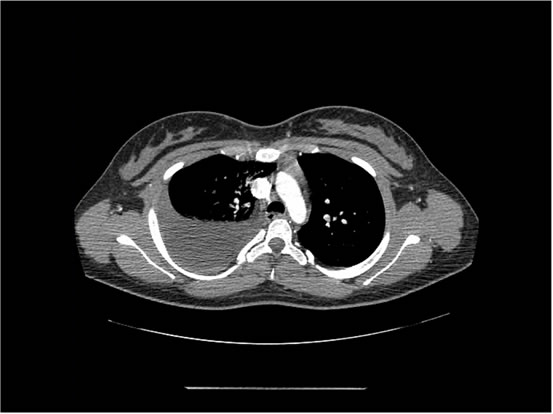

We ordered a CT scan with infusion of the chest

I will show you 12 CT-scan cuts.